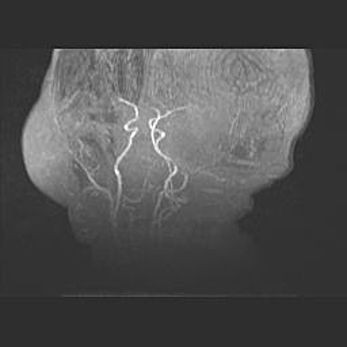

Открытая гидроцефалия.

Возраст: 9 месяцев 12 дней

Вес: 6800 г

Пол: мужской

Окружность головы: 41,5 см

Срок гестации: 28 недель

Гидроцефалия головного мозга у новорожденных имеет характерный признак: опережающий рост окружности головы приводит к визуально хорошо определяемой гидроцефальной форме сильно увеличенного в объёме черепа. Детские неврологи определяют следующие симптомы гидроцефалии у грудничков: выбухающий напряжённый родничок, частое запрокидывание головы, смещение глазных яблок к низу.